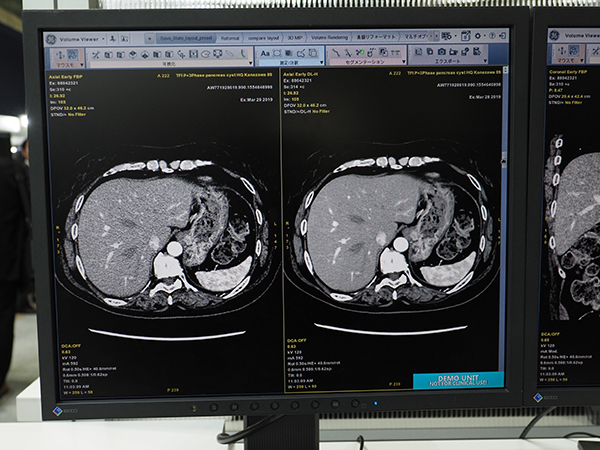

●ディープラーニングを用いて開発されたEdison PlatformのCT画像再構成アルゴリズム“TrueFidelity”

CTの展示エリアで最も注目を浴びていたのが,Edison Platformで開発されたCT画像再構成技アルゴリズム“TrueFidelity”である。今回のITEMに合わせて発表した,GEヘルスケア・ジャパンが最も力を入れてPRした展示の一つだ。

TrueFidelityは,ディープラーニングを用いて開発されており,従来の画像再構成技術とは一線を画している。CTの画像再構成技術は,近年医療被ばくへの社会的な関心が高まる中,低線量でも高画質を得るために,各社が力を入れて開発を進めてきた。GEでは,画像再構成技術として“ASiR”や“Veo”,両者を組み合わせた“ASiR-V”をCTに搭載し,医療被ばくの低減の貢献してきた。しかしながら,従来の画像再構成技術を用いたCT画像は,画質が読影する医師にとって違和感のあるテクスチャとなってしまい,特にノイズを低減すればするほど,その傾向が強くなってしまうという課題があった。

そこで,TrueFidelityでは,1970年代からCTを市場に送り出してきたGEがこれまで培ってきた画像再構成技術と,蓄積してきた画像データが生かされている。日本のエンジニアも参加しており,日本をはじめ,世界中の医師からのフィードバックを基に,FBP法で高線量で撮影した診断に適した画像を教師画像としてディープラーニングを行った。これにより,大幅に線量を落としても,高線量で撮影を行ったような鮮明な画質を得ることができる。また,全身の撮影に適用できるのも,TrueFidelityの特長である。特に,高い密度分解能が要求される頭部や腹部領域の検査で,画質を維持しつつノイズを低減し,読影する医師の負担軽減や診断能の向上に寄与する。放射線被ばくの感受性が高い小児検査でも大幅な被ばく低減が可能となる。

TrueFidelityは,ハイエンド装置の「Revolution CT」に搭載可能である。オプションとして提供されるほか,すでにRevolution CTを導入している施設には,アップグレードで対応する。Revolution CTは,RSNA 2013で発表され,2014年のITEMでお披露目された。高画質,ワイドカバレッジ,ハイスピードをコンセプトに開発され,その後,dual energy CT技術“GSI Xtream”を搭載するなど,進化を続けている。今回のTrueFidelityへの対応も,Revolution CTの大きな進化と言えるだろう。